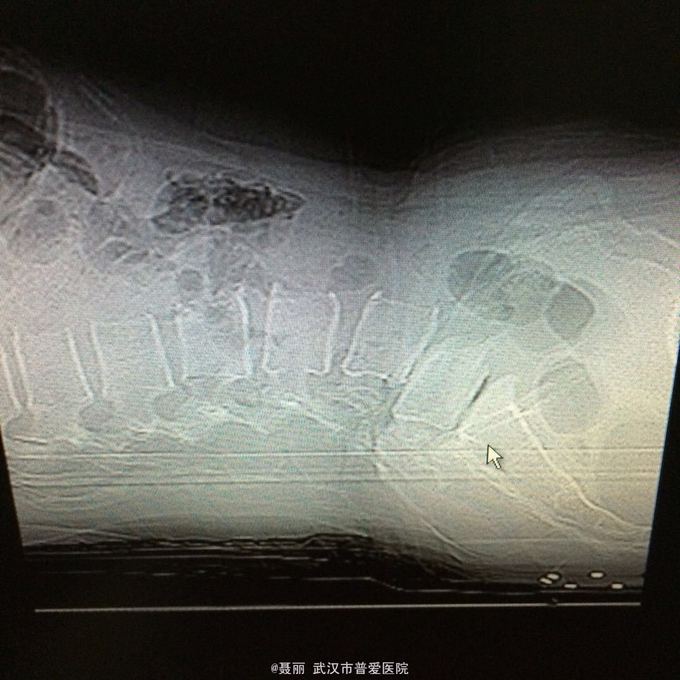

患者,女,51岁。 反复腰痛并间歇性跛行5年余,加重并左侧臀部2月余。 患者于5年前无明显诱因外伤诱因出现腰痛,不伴有双下肢麻木、乏力及间歇性跛行,卧床休息后好转,间歇发作,进行性加重。 既往史:有高血压病、糖尿病病史,否认有药物过敏

:L4/5棘突间轻压痛,叩痛,棘间左侧椎旁压痛;双下肢肌力、肌张力正常,病理反射未引出。 门诊资料:外院行腰椎CT检查示:L3-S1椎间盘膨出,L4椎弓崩裂并向前滑脱(重度)椎管狭窄。 入

入院诊断:、腰椎滑脱(L4/5 峡部裂性) 诊疗计划:1:完善有关检查2卧床休息,行改善微循环、3.腰椎后路复位减压植骨融合术